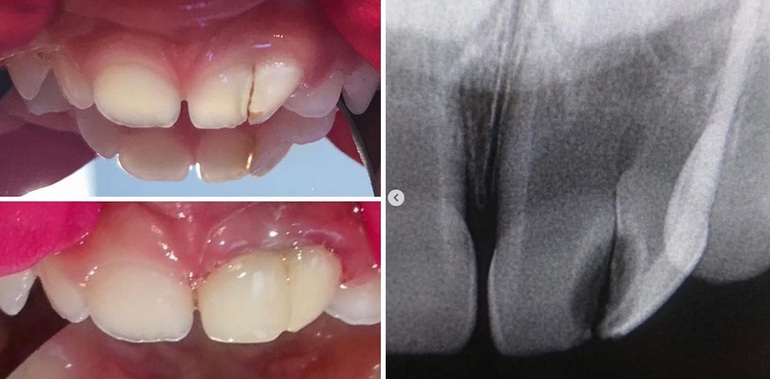

лечение_без_болиДва передних зубика у ребенка выросли спаренными - образовались так называемые «сросшиеся» зубки и между ними возник кариес. Дома, в Латвии, родители не нашли клиники и врача, чтобы исправить эту ситуацию. Им предлагалось только удаление этих зубов без какой-либо альтернативы...

Но зубная фея Инна Игоревна Склярова доказала обратное. Она вылечила и восстановила зубки за один прием.

Теперь у девочки, к счастью, все хорошо. Зубки здоровы и будут стоять на своих местах, до прихода постоянных и выполнять свою функцию.